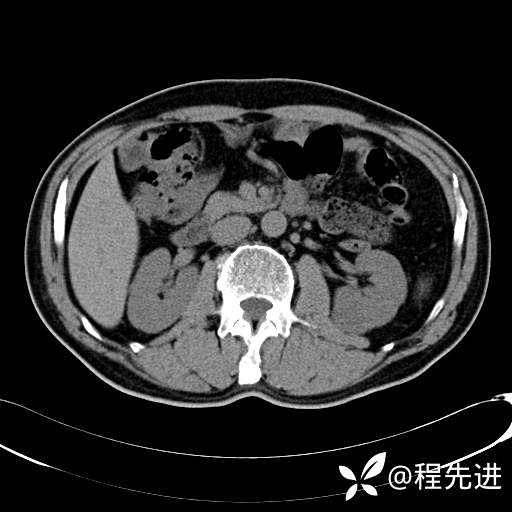

患者性别:男

患者年龄:65岁

简要病史:腰痛2月,体检发现左肾占位5天

平扫: